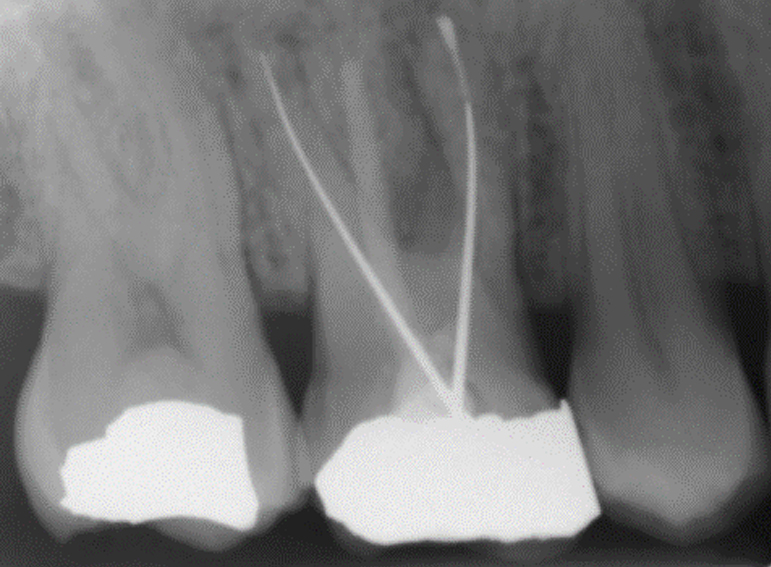

Separated instrument management on a sclerosed upper second molar.